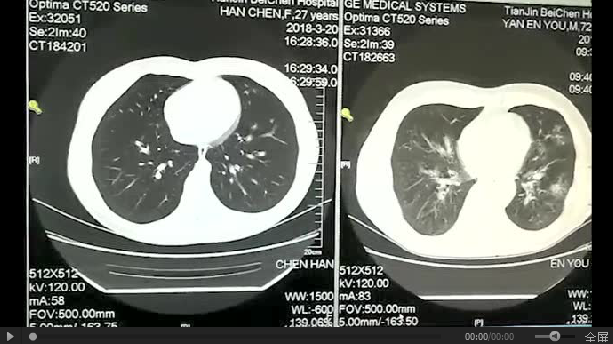

这是在感染科病房采集的肺部CT对比图

左侧为健康人的肺 右侧为吸烟40年的肺